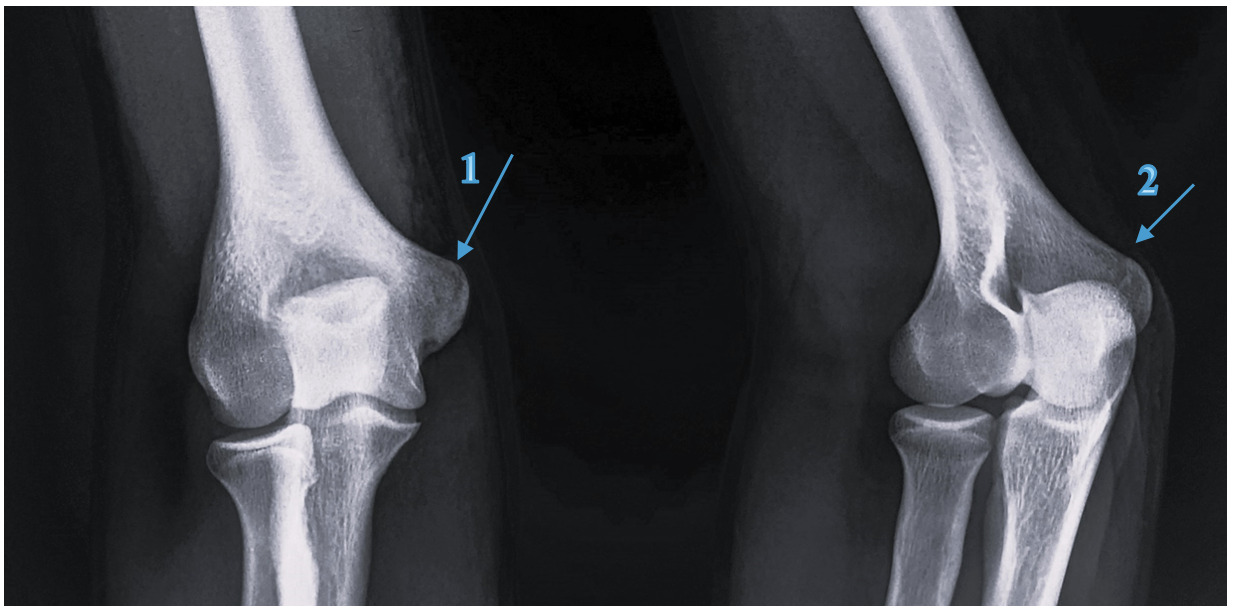

A 15-year-old amateur male Javelin thrower (State Representative) presented with a swollen and painful right elbow after throwing javelin in a competition three days prior to the appointment. The pain was felt immediately after releasing the javelin on his third throw of the competition with a 9/10 (NRS) pain and he was forced to withdraw. The pain remained 5/10 (NRS) for the following 7 days. Athlete E had been experiencing pain in the right elbow and forearm during the preceding month at training and competition, stating he had some discomfort after most training sessions. On physical examination, active full elbow flexion (45°) and extension (140°) was apprehensive and tuning fork vibration test over the medial epicondyle recorded a positive 7/10 pain (NRS) shown in Table 2, therefore referred for x-ray. The x-ray, Figure 4, revealed an avulsion fracture to the medial epicondyle with no displacement. Other clinical and associated findings uncovered during the physical examination were consistent with medial epicondylitis.

Athlete E

The initial management for Athlete E was complete rest from training and competition, with chiropractic therapy, as presented in Appendix A. Conservative rehabilitation was initiated at 14 days which included wrist mobility and forearm flexibility exercises, as outlined in Appendix B. The athlete achieved an ‘Excellent’ on the Conway scale37 and returned to Javelin competition at 18 weeks throwing 98.2% of PB 54.12m (700g), with an improvement of 3.2% to 56m (700g) after 26 weeks.

The sports chiropractors decided not to refer Athlete B for imaging, rather using their clinical experience, the athlete’s history and clinical presentation to make a working diagnosis of pathological findings and initial conservative management. Athlete E was referred for x-ray (Figure 4) 5 days post injury incident to confirm a fracture to the medial epicondyle (Little Leaguers Elbow), after clinical examination suggested its likeliness.